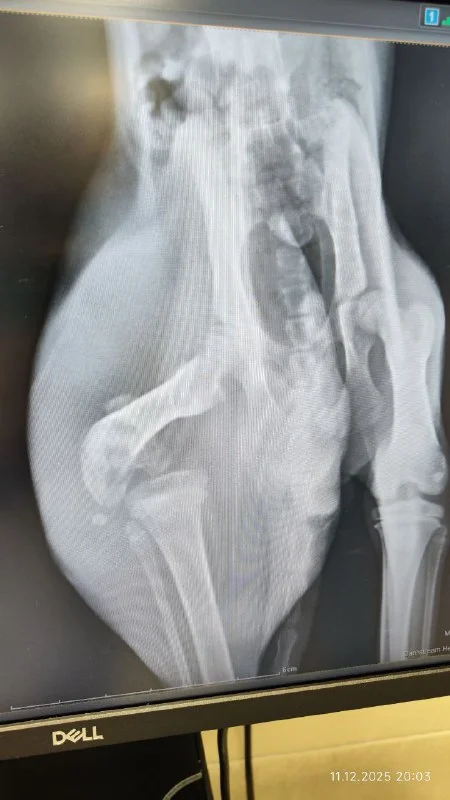

Здравствуйте. Прошу помощи с котенком. Нашла в тяжёлом состоянии. Сейчас наблюдается у доктора Христоса в Small animals. После вскрытия абсцесса и нескольких дней антибиотиков у него появились силы двигаться и жалобно мяукать. Операция предстоит в субботу. Но, инфекция продолжает разрушать кость. Если она остановится, то которебенку наложат скобу ,если нет ,то ампутация задней лапы. Котенок уличный, у меня есть возможность выходить его и выпустить на улицу после того ,как лапка заживёт, но нет возможности его взять к себе ,если лапу ампутируют, а на улице он не выживет без неё. И тогда выход усыпление, чтобы не мучить живое существо. Если в субботу не найдется добрый души человек, кто может трехлапого взять себе,то его усыпят. Я готова взять расходы на себя по операции, восстановлению, прививкам, но тщательно подумав и всё взвесив, я не могу его оставить себе .

позвонили из клиники, хоть вчера котенку было лучше, сегодня он совсем плох, видимо пошло заражение крови. Спрашивают усыплять сейчас или оставлять до завтра?

У котенка гипотермия и так как инфекция уже в кости говорят что также заражение крови. Он получает антибиотики и под капельницей, но если его состояние не улучшится операцию сделать не смогут, так как он не сможет перенести наркоз. Также говорят может потребоваться переливание крови.